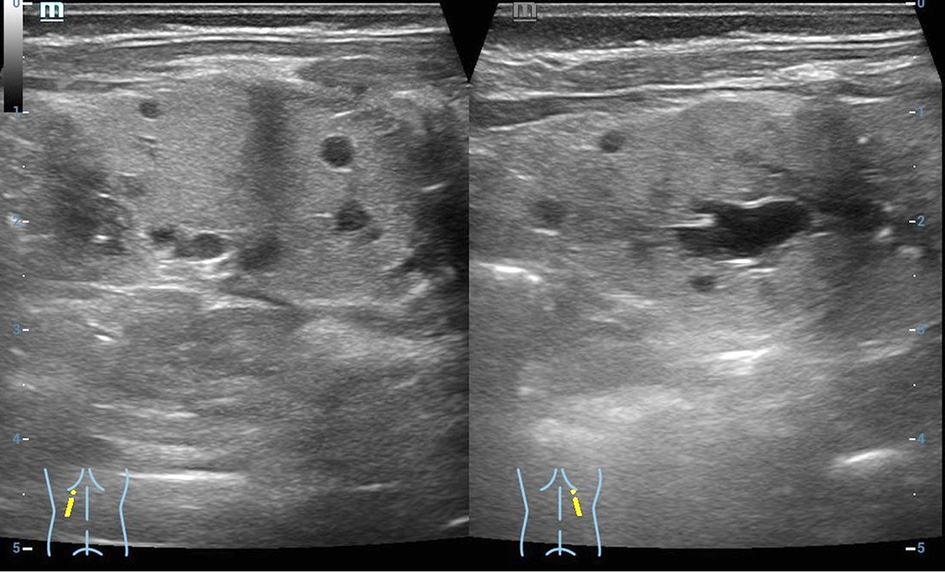

A baby girl was born after in vitro fertilization at 37 weeks of gestation (the labor was induced due to maternal preeclampsia) by vaginal delivery. At birth, her anthropometric measurements were as follows: weight 2320 g (<5th centile), height 50 cm (25th centile), and occipitofrontal circumference 33 cm (50th centile). Apgar scores were 8 and 9 at 1 and 5 min, respectively. Bilateral hyperechogenic kidneys were observed in fetus at 31st week of gestation on prenatal ultrasound. Due to moaning infant was observed in the neonatal pathology ward for 9 hours. On the 3rd day of age, she developed a neonatal jaundice. Values for total bilirubin were elevated in capillary blood (438 µmol/L) and in venous blood (296 µmol/L). Laboratory testing showed metabolic acidosis (serum HCO3 17 mmol/L), hypercalcemia (ionized calcium 1.55 mmol/L). The neonate kidney ultrasound revealed poor corticomedullary differentiation, thickened parenchyma and small multiple cysts. No nephromegaly was observed (Figure 1). Renal function was impaired: increased creatinine (162 µmol/l) and reduced GFR (11 mL/min/1.73 m2). Urinalysis showed glucosuria (17 mmol/L), proteinuria (0.25 g/L), microhematuria (10/µl). The newborn was treated with a phototherapy and intravenous fluid infusion, sodium bicarbonate for the correction of metabolic acidosis. Total bilirubin went back to normal after two days of phototherapy, while metabolic acidosis was corrected after one week of treatment. The newborn was consulted by a pediatric nephrologist and clinical geneticist. Family history revealed: the mother was a 30-years old woman diagnosed with chronic kidney disease stage 3 (creatinine 122 µmol/L, GFR 51 ml/min/1.73 m2), diabetes mellitus at the age of 22, and had a 4-year history of unexplained primary infertility as well as hypertensive retinopathy. Her kidney ultrasound showed hypoplastic left kidney (left kidney 8.49 cm, parenchyma 1.13 cm; right kidney 10.86 cm, parenchyma 1.91 cm), bilateral kidney parenchymal cysts (1.35 to 2.29 cm in size), subcapsular microcalcinates, and reduced corticomedullary differentiation. At the age of 29 she was evaluated for infertility. Her gynecological examination results were normal, while laparoscopy and hysteroscopy findings included endometriosis and intrauterine polyp, respectively. Assisted reproduction attempt was performed without genetic counselling. At the time of pregnancy her BMI was 30.11 (class 1 obesity). Mild preeclampsia has been observed during pregnancy.

Figure 1. Patient kidney ultrasound. Increased echogenicity of the renal parenchyma on both sides, poor corticomedullary differentiation, thickened parenchyma, small multiple cysts in the parenchyma from immeasurable to 0.6 cm. The size of both kidneys 5 × 2.1 cm.